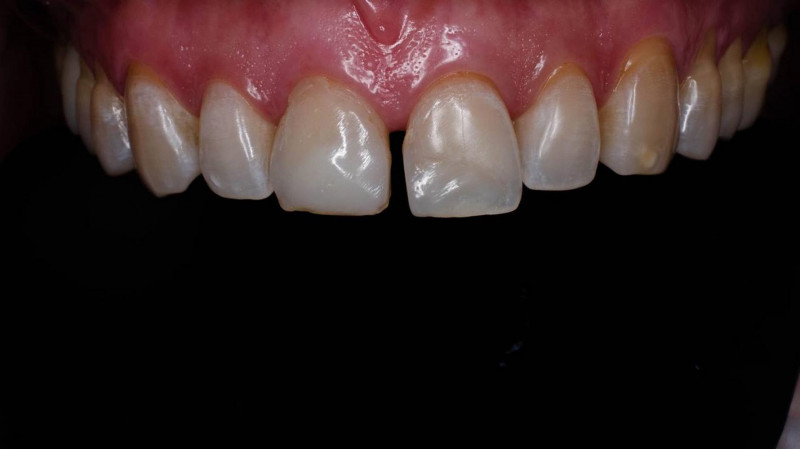

Установка керамической коронки

Протезирование зуба 12 керамической коронкой @po_makedonsky спасибо за работу

Доктор: Капитонова Екатерина Андреевна